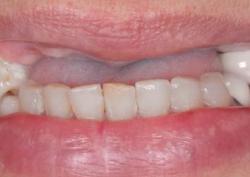

Примеры протезирования зубов

Каждый день мы помогаем восстанавливать улыбку нашим пациентам.